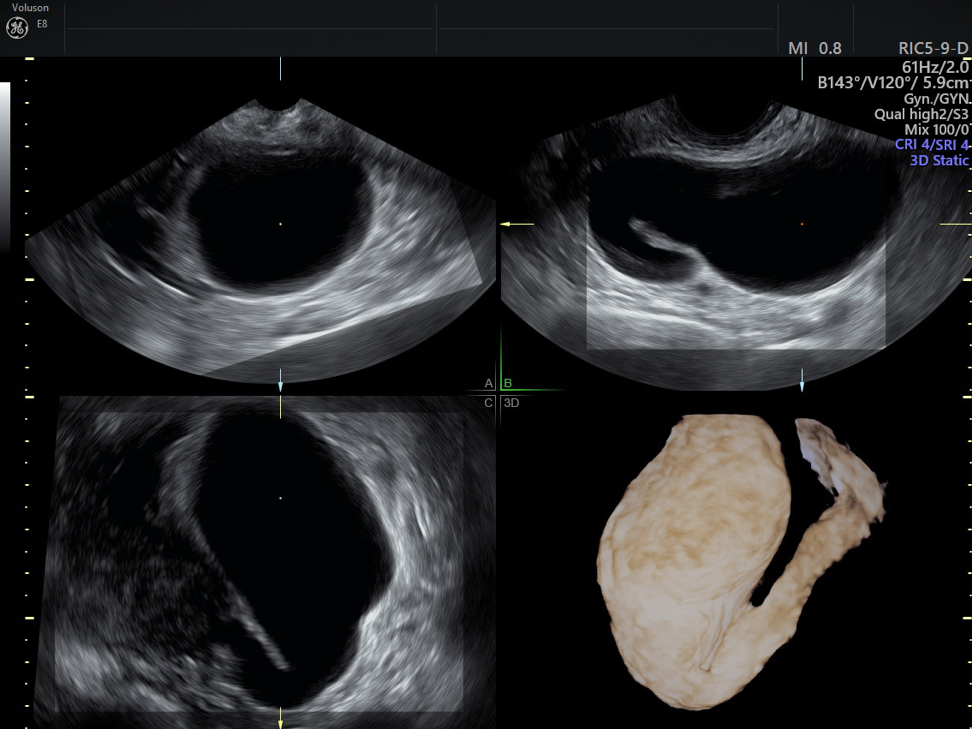

How to Use 3D Ultrasound in Hydrosalpinx Treatment Empowered Women's